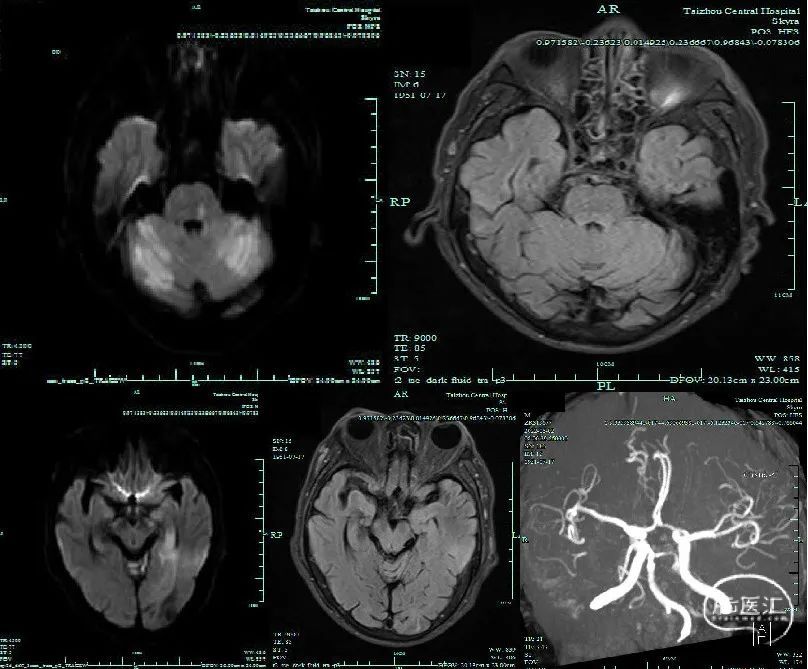

头颅MR:DWI提示左侧脑桥基底部、双侧小脑半球、左侧颞叶急性梗死,与FLAIR不匹配,左侧P2段不显影。